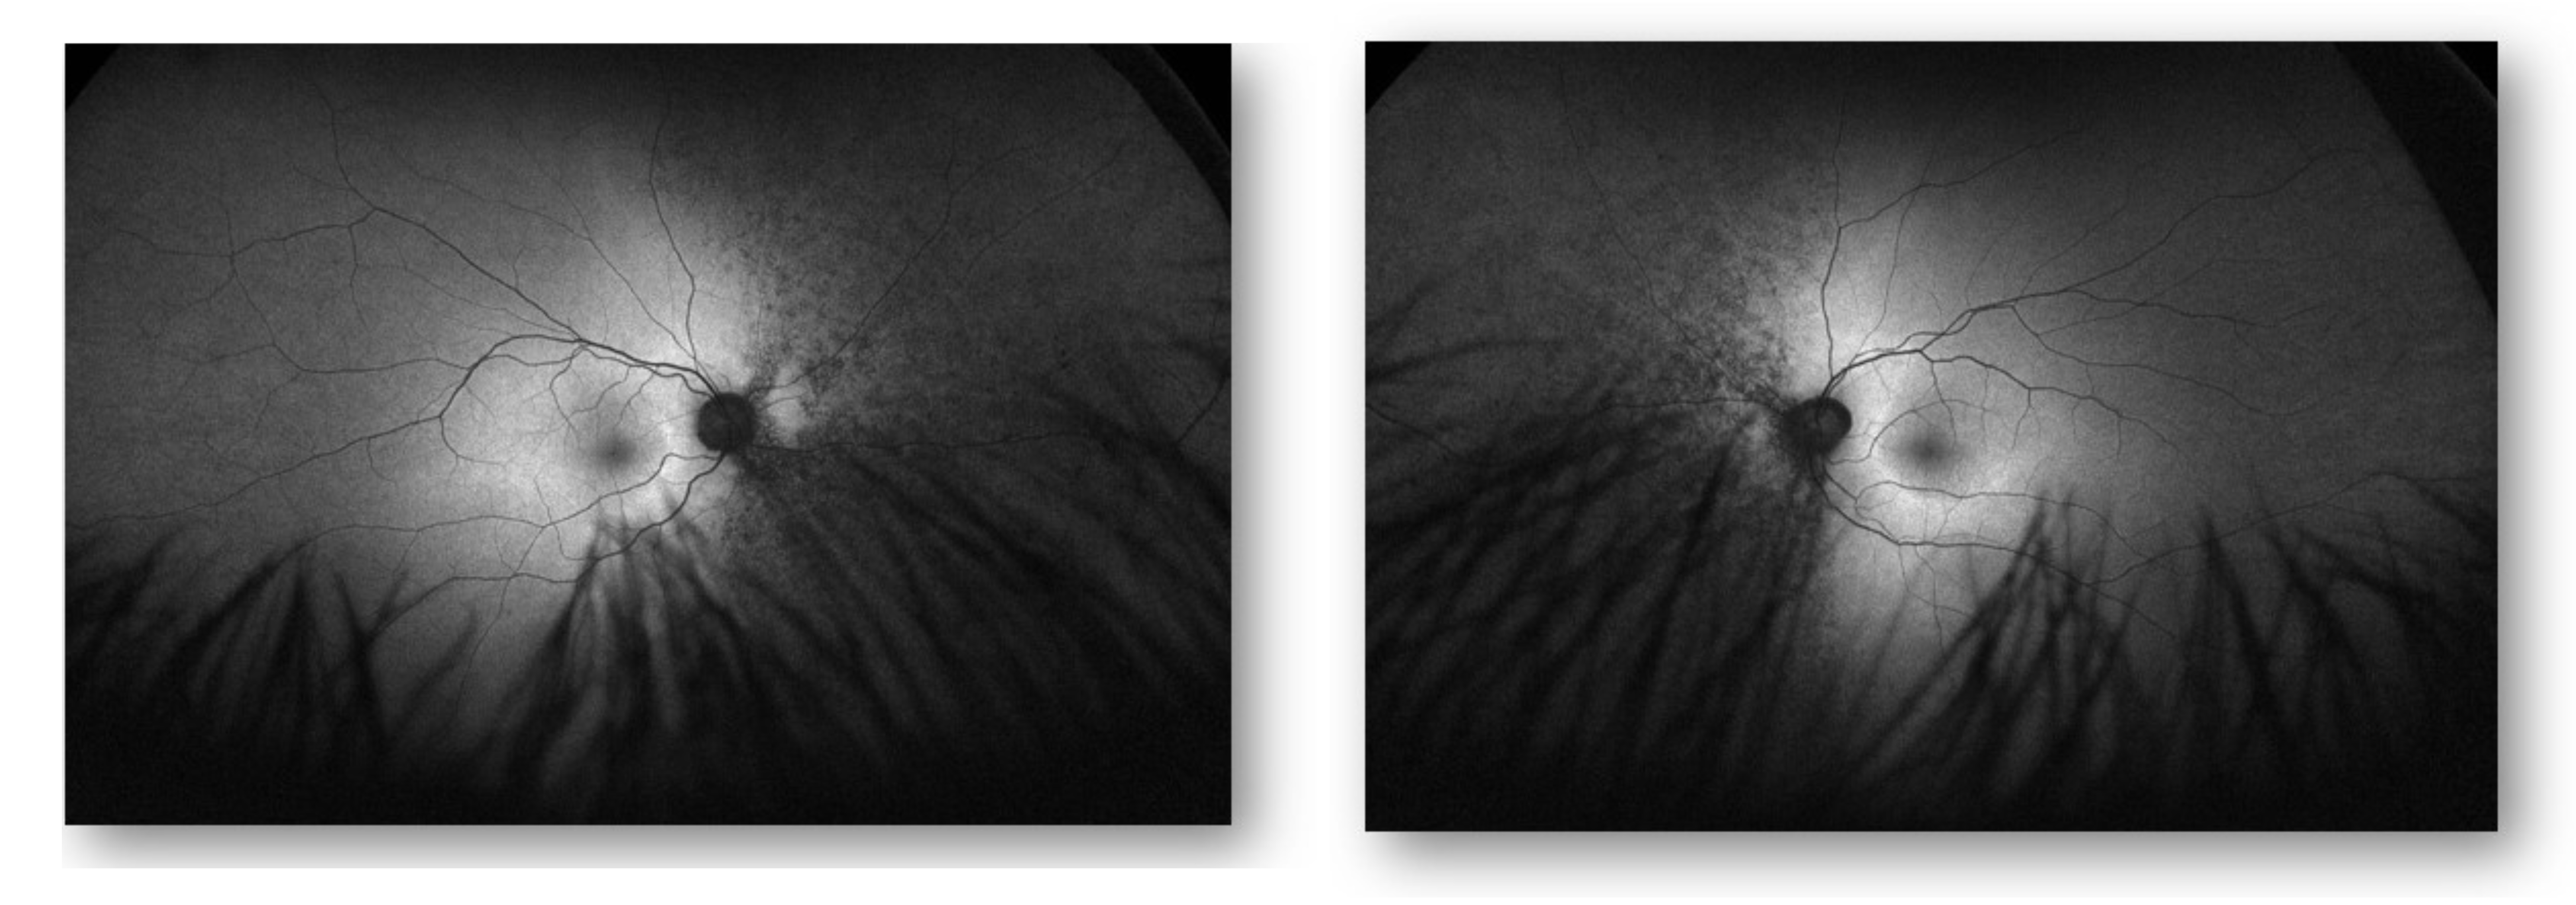

Figure 2:

Auto Fluorescence OD Auto Fluorescence OS